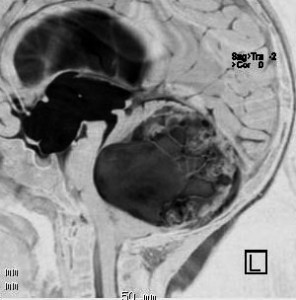

思春期の女の子にできた小脳腫瘍です。とても大きく見えますがほとんどが水たまり(のう胞といいます)。第4脳室が腫瘍で圧迫されて閉塞性水頭症になりました。のう胞の中に出血がありますが毛様細胞性星細胞腫では腫瘍内出血をしばしば見ます。右の写真で脳室が大きくなっています。こんなに大きいのに小脳症状は全くなくて,頭痛と嘔吐が症状でした。

赤で塗ったところだけが毛様細胞性星細胞腫です。これを取れば治ります。簡単な手術ですし後遺症も残りません。

手術後のMRIです。水頭症も改善してますから症状も消失しましたし,すぐに退院です o(^o^)o